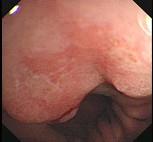

问题 男性54岁,间歇性上腹部不适4年,餐后加重,嗳气来诊。胃镜检查如图,应采取下列哪种治疗方法为宜 ( )

选项 A.西咪替丁 B.吗丁啉 C.吗丁啉+法莫替丁 D.洛赛克 E.手术治疗

答案 E